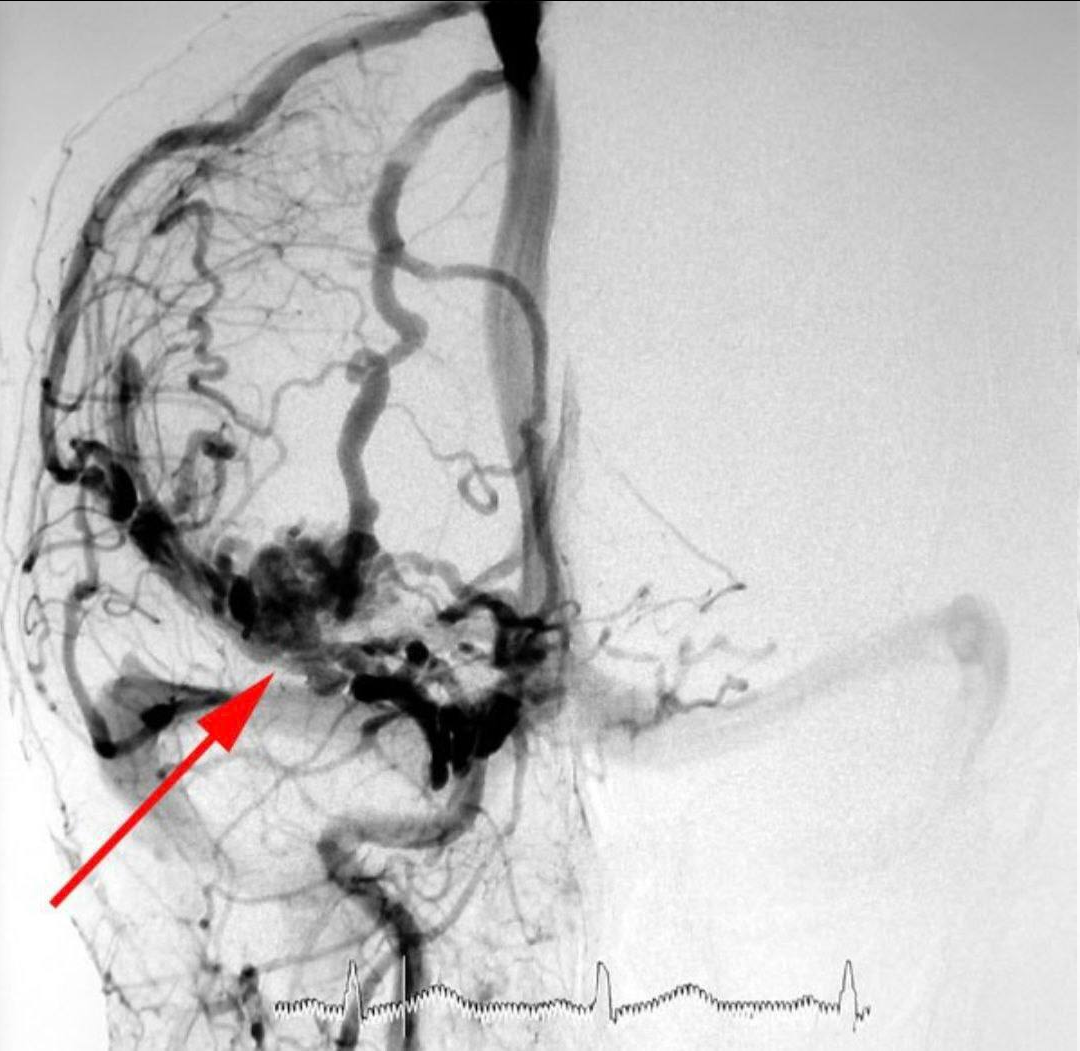

Удаление авм

Удаление авм 115 фото